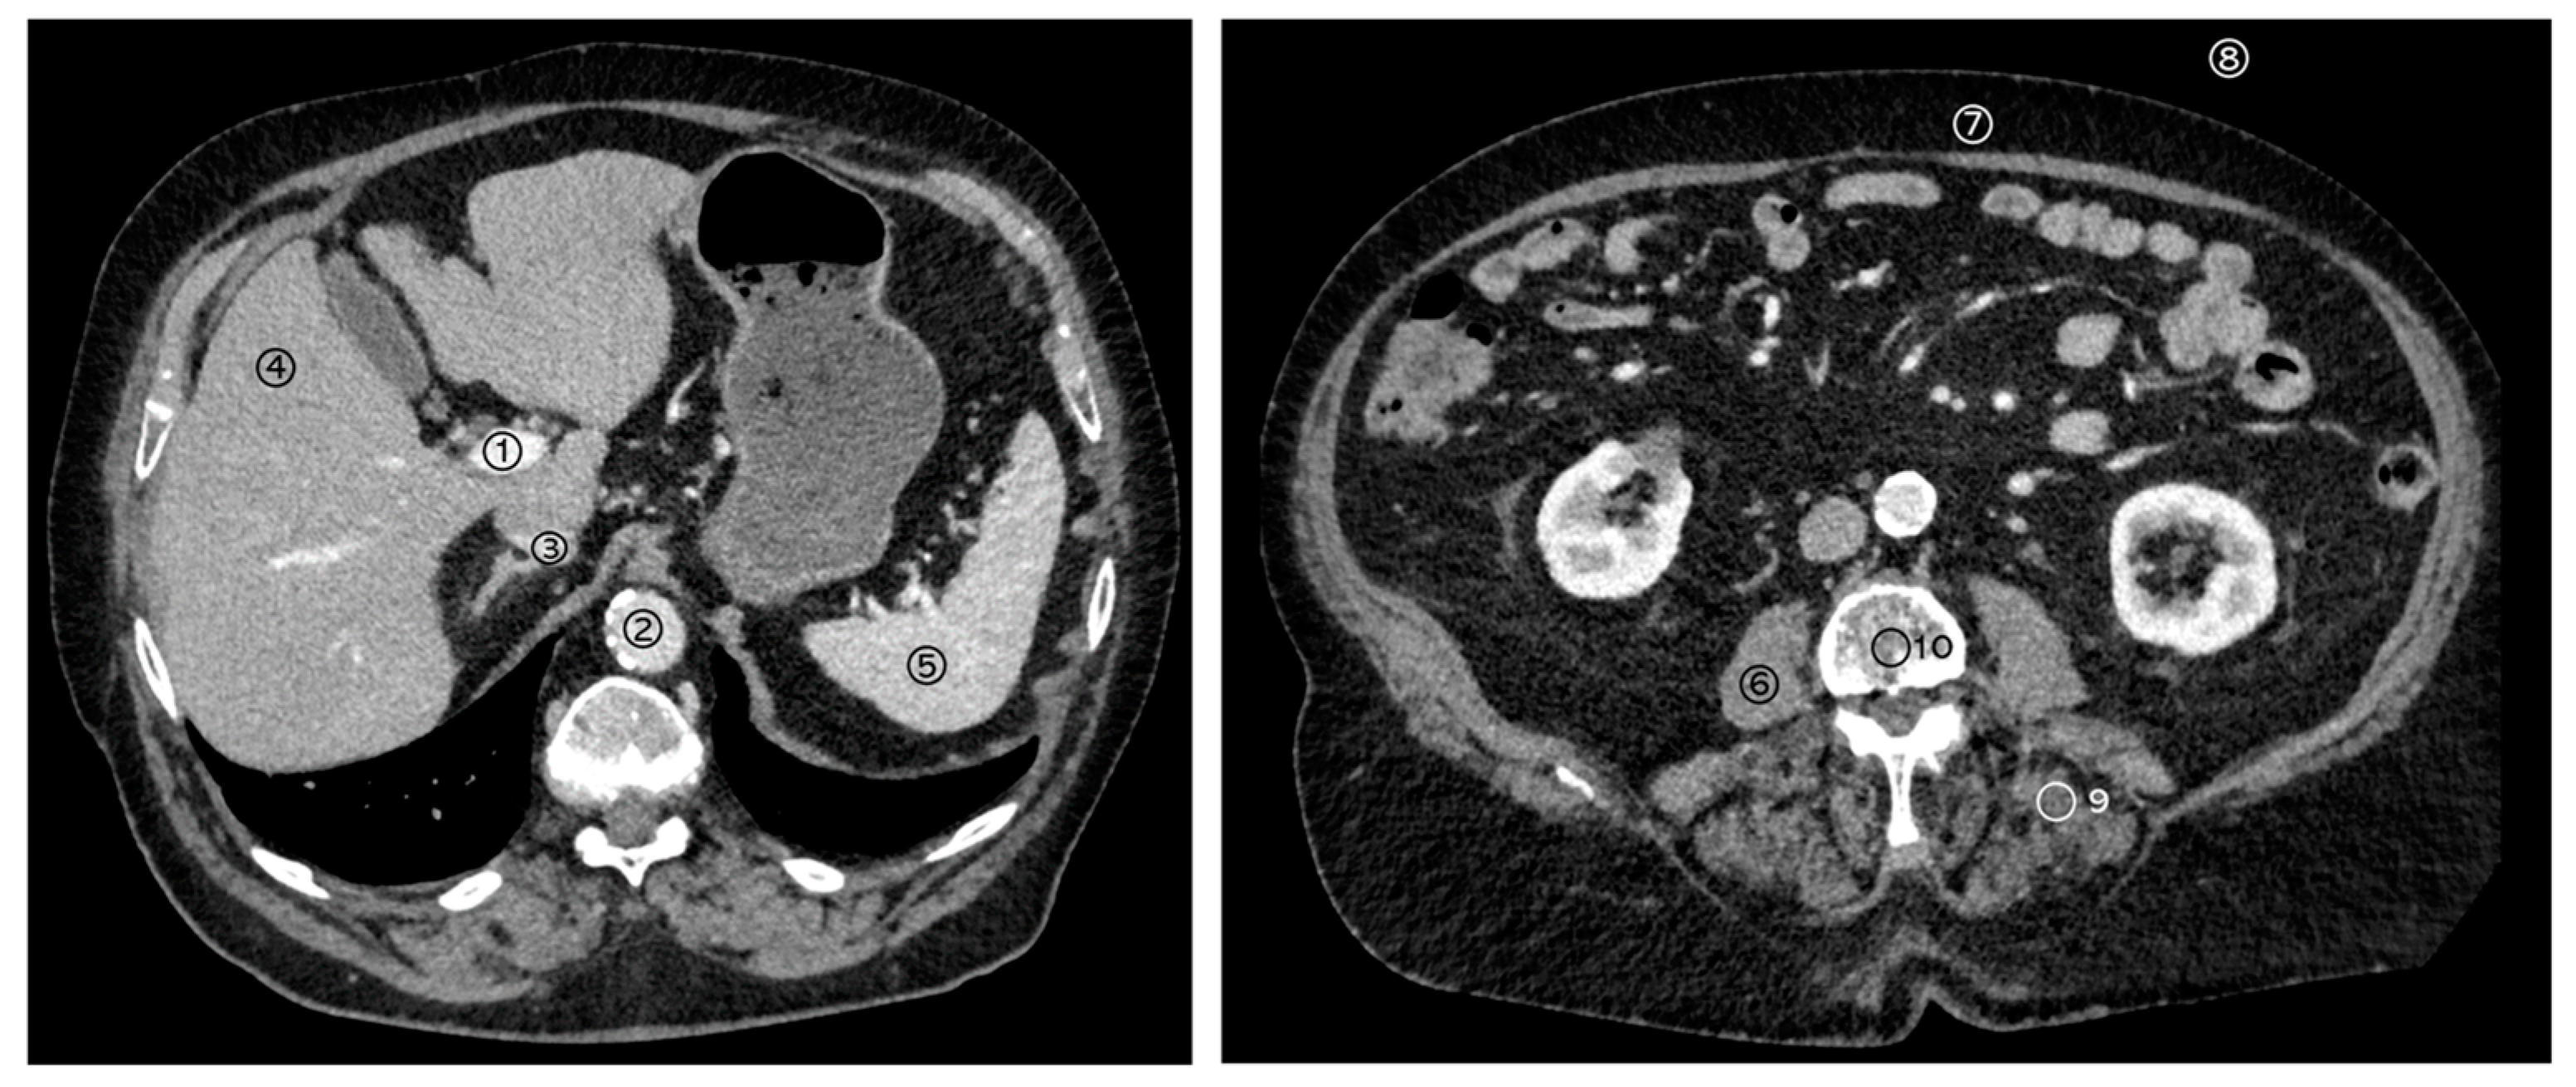

2.3. Structured Measurements